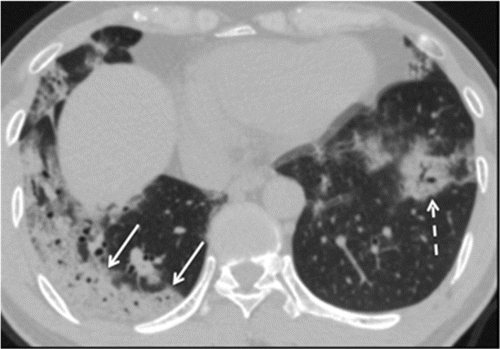

Tomografías computarizadas de pacientes con lesión pul- monar inducida por radiación ... |

... coinciden casi exactamente con las tomadas a pacientes infectados con la enfermedad del coronavirus COVID-19 |